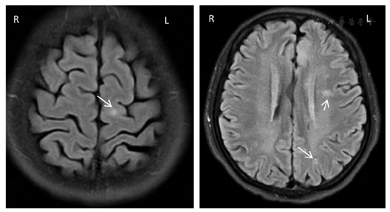

腹部彩超:多囊肾声像图改变;双肾结石;双侧输尿管无扩张;肝内实性病灶;肝多发囊肿;胆胰脾未见明显异常。心电图及心脏彩超未见明显异常。全腹部CT平扫(图1):双肾改变,考虑多囊肾、部分为复杂囊肿,合并多发错构瘤,以左肾为显著;肝内多发低密度灶,囊肿。胸部CT平扫(图2):双肺多发囊腔,考虑肺淋巴管肌瘤。胸椎及肋骨多发结节状高密度灶。头颅MRI平扫(图3):双侧额叶、左侧顶叶、右侧颞叶皮质及皮质下结节状异常信号。

由于TSC1、TSC2基因突变导致TSC合并多囊肾的发病率也明显高于普通人群。2012年国际结节性硬化症共识会议对TSC诊断标准进行了修订[1],将基因检测列为独立的诊断标准,通过基因检测可鉴定出TSC1或TSC2致病突变即可确诊TSC。15%~25%的TSC患者通过常规基因检测未能检出突变,故基因检测阴性不能排除TSC,亦不作为TSC诊断金标准。当临床诊断疑似时可行基因诊断。临床诊断标准包括:主要特征:(1)色素脱失斑(≥3个,直径≥5 mm);(2)面部血管纤维瘤(≥3个)或头部纤维性斑块;(3)甲周纤维瘤(≥2个);(4)鲨革斑;(5)多发性视网膜错构瘤;(6)脑皮质发育不良(包括结节和脑白质辐射状迁移线);(7)室管膜下结节;(8)室管膜下巨细胞星形细胞瘤;(9)心脏横纹肌瘤;(10)肺淋巴管肌瘤病;(11)肾脏血管平滑肌脂肪瘤(肾错构瘤)。次要特征:(1)"斑驳状"皮肤改变;(2)牙釉质点状凹陷(≥3个);(3)口腔内纤维瘤(≥2);(4)视网膜色素缺失斑;(5)多发肾囊肿;(6)非肾脏错构瘤。具有2个主要特征,或1个主要特征加2个次要特征可确诊;具有1个主要特征,或1个主要特征加1个次要特征,或≥2个次要特征为疑似。

TSC可累及多脏器多系统,根据发病年龄受累器官不同,其临床表现也不尽相同。有学者将其主要临床表现归纳为血管纤维瘤、癫痫发作及智力减退三联征。本例患者无上述临床表现,诊断上易出现误诊、漏诊。本例患者TSC诊断得益于腹部、胸部及头颅影像学对各系统检查提示:同时具有多个肾错构瘤、肺淋巴管肌瘤、大脑皮质及皮质下多发结节3个主要特征及多发肾囊肿1个次要特征。患者目前规律随访中,病情无进展。根据2012年TSC专家共识院外仍需定期进行腹部及头颅影像学检查,及对肾小球滤过率及血压进行定期评估。TSC为常染色体显性遗传,疾病根据个体发育阶段的不同而有不同发展。患者儿子患多囊肾,进一步腹部、头部影像学检查有助于排查有无脏器受累。基因检测亦可用于遗传咨询或诊断不明确情况下。